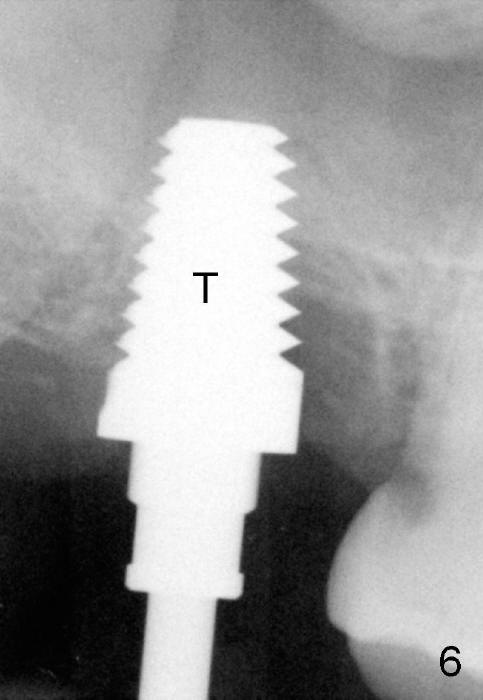

By contrast the palatal socket is deep and relatively small (Fig.4 P), easy to insert taps without drills. When a 7x11 mm tap is placed (Fig.5 T), the coronal end is more or less near the lingual cusps (functional cusps). Although the 7x14 mm tap (Fig.6 T) and a 7x11 mm implant (Fig.7 I) look poking into the maxillary sinus, they are in fact within the palatal socket (Fig.10c). Allograft and Osteogen are placed in the buccal socket (Fig.7 *), followed by collagen dressing (Fig.8 *). A 5x5 mm abutment is placed (Fig.8 A). An immediate provisional (Fig.9 P) is cemented to keep the graft and collagen dressing in place.